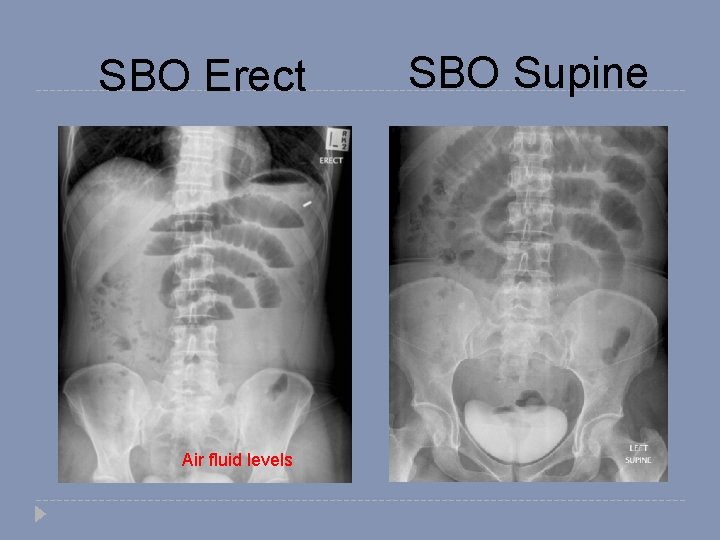

Mechanical SBO � Dilated small bowel � Fighting loops (visible loops, lying transversely, with air-fluid levels at different levels) � Little gas in colon, especially rectum

SBO Erect Air fluid levels SBO Supine